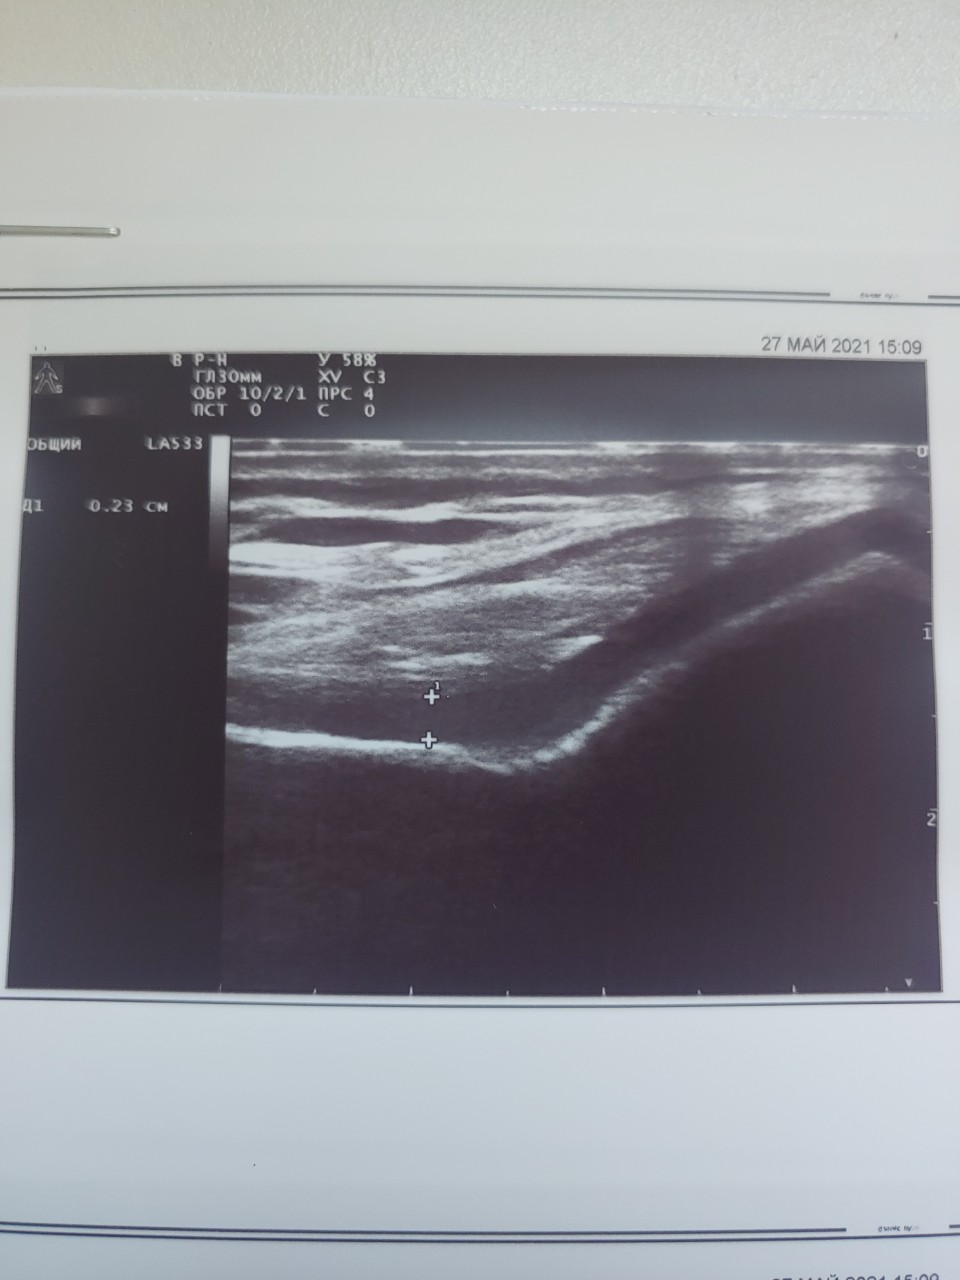

УЗИ коленных суставов Вам не делали?

Благодарю за внимание! Делали, в выписке если Вам не сложно можно посмотреть (загружены сканы к вопросу)

Прошу прощения, не заметил. В любом случае, они не делали исследование в режиме энергетического допплера, а это при подозрении на артрит самое главное.

Здравствуйте, уважаемый Андрей Анатольевич! Можно попросить Вас оценить состояние суставов сына. Сделано УЗИ в режиме Допплера (если это действительно так) Сейчас жалоб нет, единственное, что или просто боится сесть на корточки, или не позволяют ощущения. Говорит что не может до конца согнуть колени (угол сгиба примерно 45-50 градусов). Но, например, у меня самого в колене нога тоже до конца не сгибается, 30-40 градусов. СРБ и СОЭ сейчас, как и раньше, в норме. Очень хочу перевести лечение с метотрексата на Сульфасалазин + Метилпреднизолон по Вашей схеме.

Здравствуйте! Высылаю описание УЗИ.

По узи у ребёнка нет признаков артрита. Энтезиты более характерны для псориатического артрита.